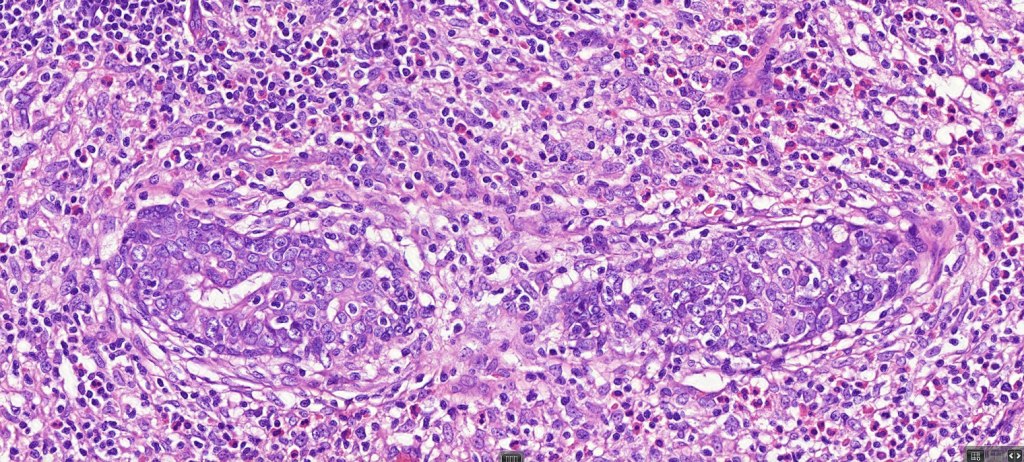

Histological features

•Follicular infiltration by atypical lymphocytes & Sézary cells

•Eosinophils sometimes conspicuous (eosinophilic folliculitis-like appearance)

•Granulomatous inflammation secondary to follicular destruction

•Large cell transformation occasionally present